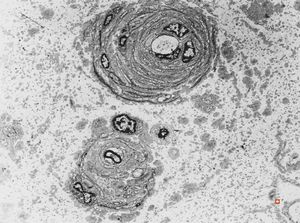

F,23y. | - n.suralis- hypertrophic demyelinizing neuropathy (onion bulbs)

F,23y. | - n.suralis- hypertrophic demyelinizing neuropathy (onion bulbs)